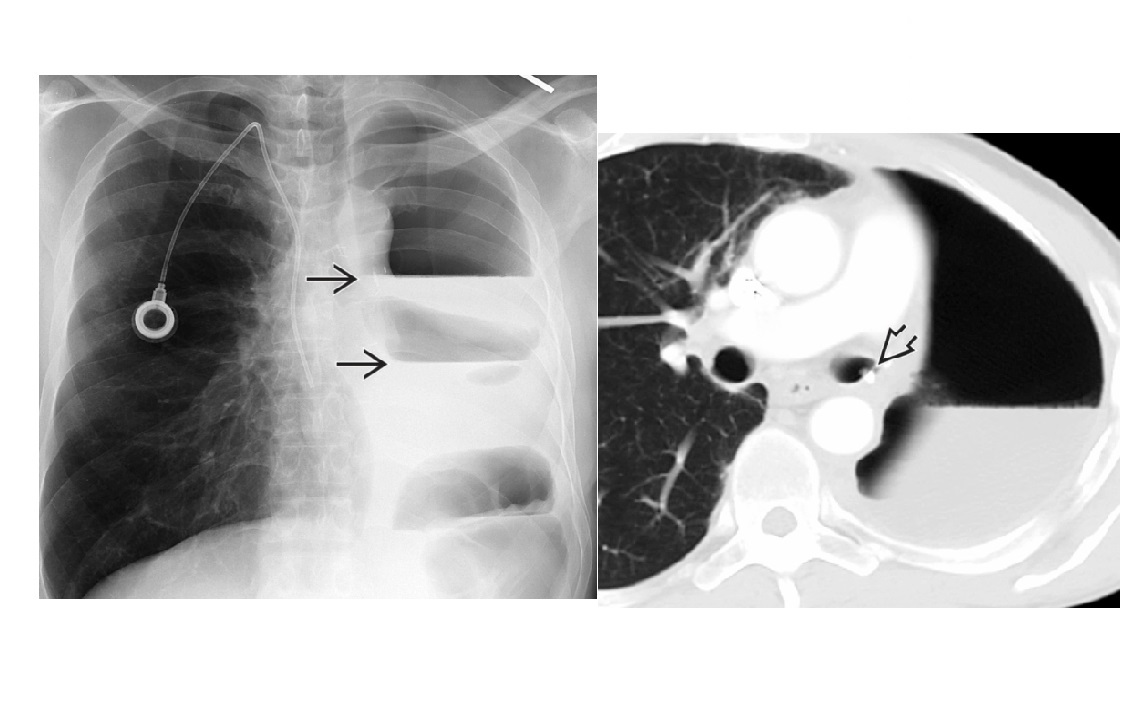

18

NSIP

CT

Absent (less) / microcystic honeycombing

Bilateral ground-glass &/or reticular opacities

Traction bronchiectasis/bronchiolectasis

Relative Subpleural sparing

peribronchovascular fibrosis

Most hunt for assocation/cause on CT

?dilated oesophagus - scleroderma

? joint disease - RA

?portcath/PICC - chemotherapy

sjorgens

HIV